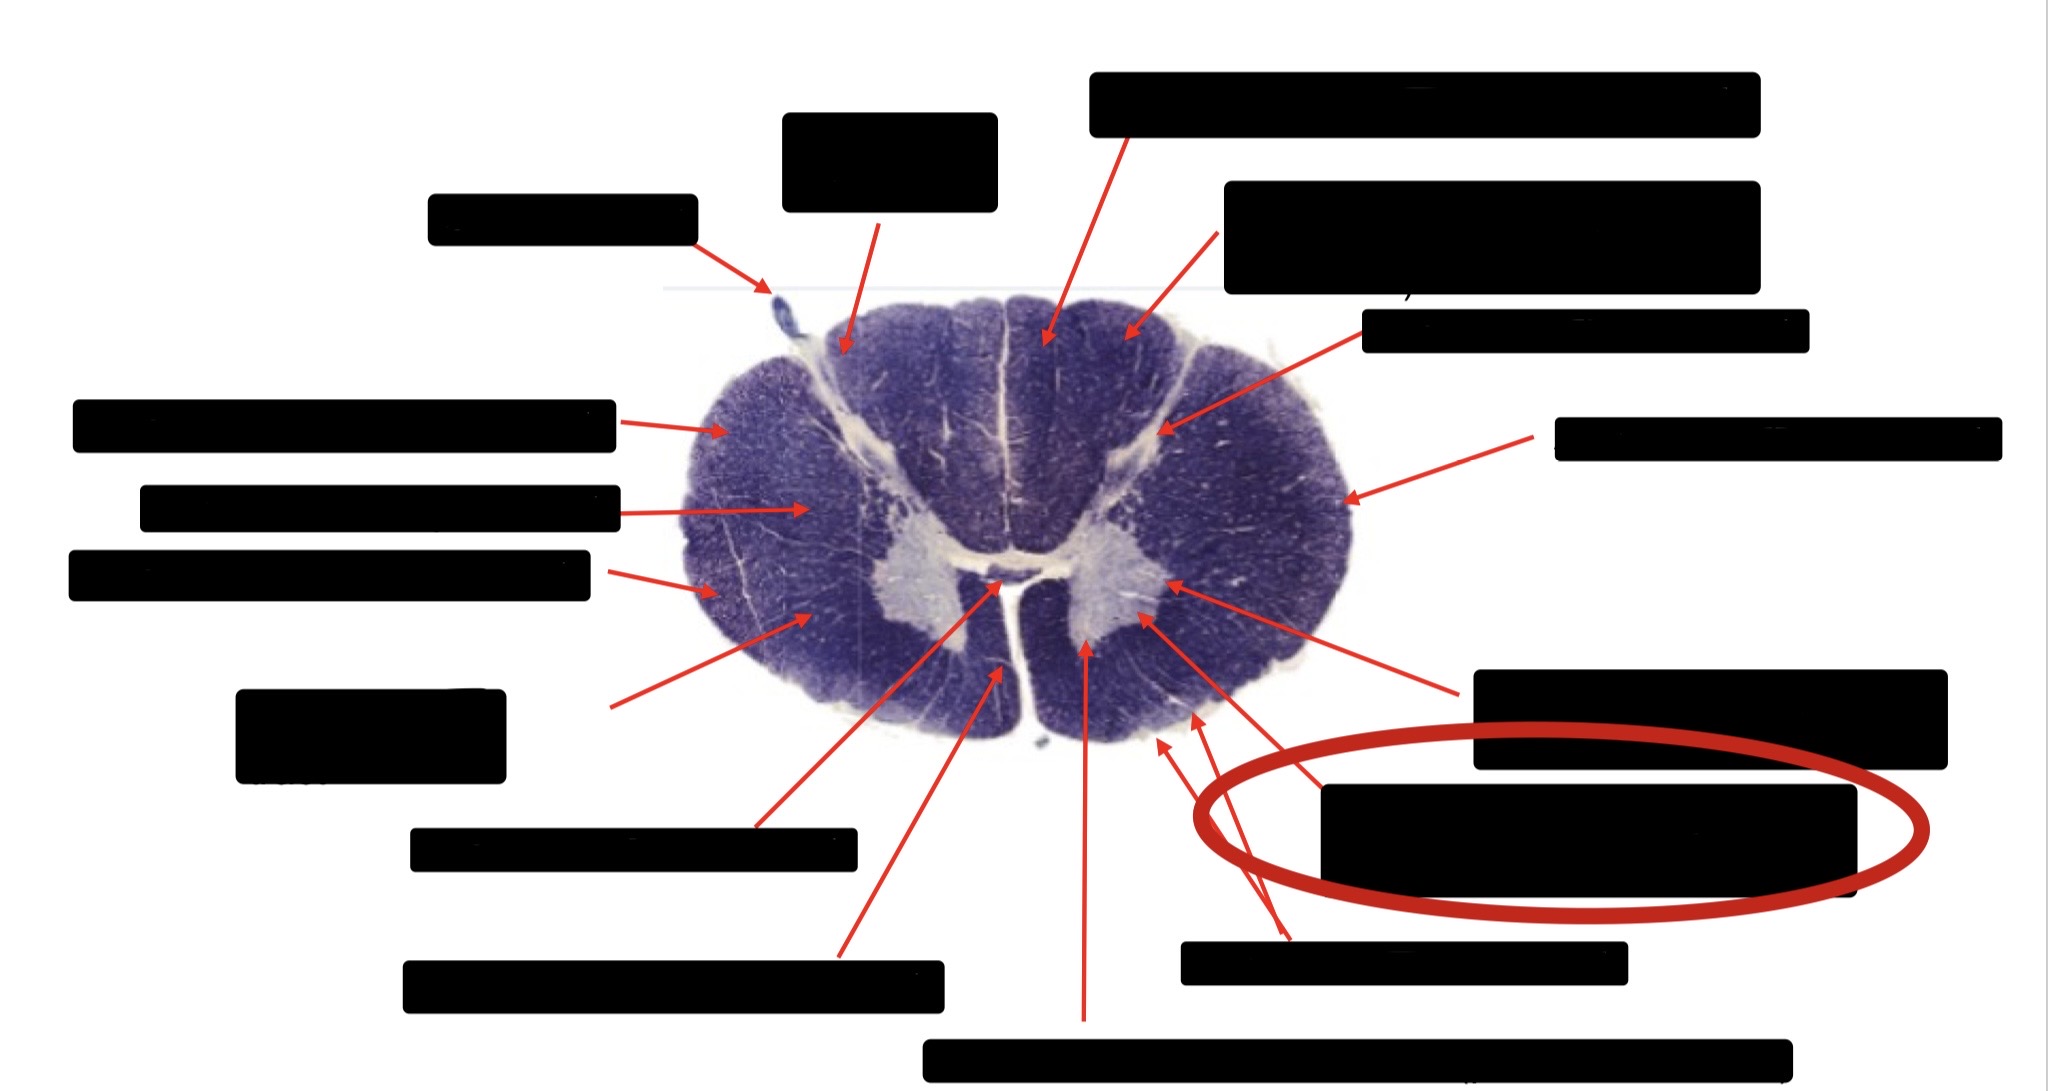

Central Canal

Posterior Column (Fasciculus Gracilis)

Large Fiber Entry Zone

Lissaeur’s Tract & Small Fiber Entry Zone

Substantia Gelatinosa

Lateral Corticospinal Tract

Ventral Root Fibers

Anterior Horn Motor Neurons

Anterior Medial Fissure

Dorsal Rootlet

Posterior Spinocerebellar Tract

Anterior Spinocerebellar Tract

Spinothalmic Tract

Posterior Column (Fasciculus Cuneatus)

Anterior Horn Motor Neurons (Distal Muscles)

Anterior Horn Motor Neurons (Proximal Muscles)

Anterior Corticospinal Tract

Accessory Nerve Fibers

Anterior Horn Motor Fibers (Accessory Muscles)

Anterior Horn Motor Fibers (Proximal Muscles)

Anterior Horn Motors Neurons (Proximal Muscles)

Posterior Columns (Joint Position, Vibration, Pressure)

Fasciculus Cuneatus

Fasciculus Gracilis

Dorsal Root

Dorsal Spinocerebellar Tract

Ventral Spinocerebellar Tract

Lateral Spinocerebellar Tract (Pain & Temperature)

Ventral Root

Anterior Horn (Motor Neurons)

Distal Limb Movements

Lateral Corticospinal (Pyramidal Tract)

Rubrospinal Tract

Axial & Proximal Limb Movements

Lateral Reticulospinal Tract

Vestibulospinal Tract

Ventral Reticulospinal Tract

Tectospinal Tract

Ventral Spinthalamic Tract (Pressure Touch - Minor Role)

Ventral (Uncrossed) Corticospinal Tract (Distal Limb Movements - Minor Role)